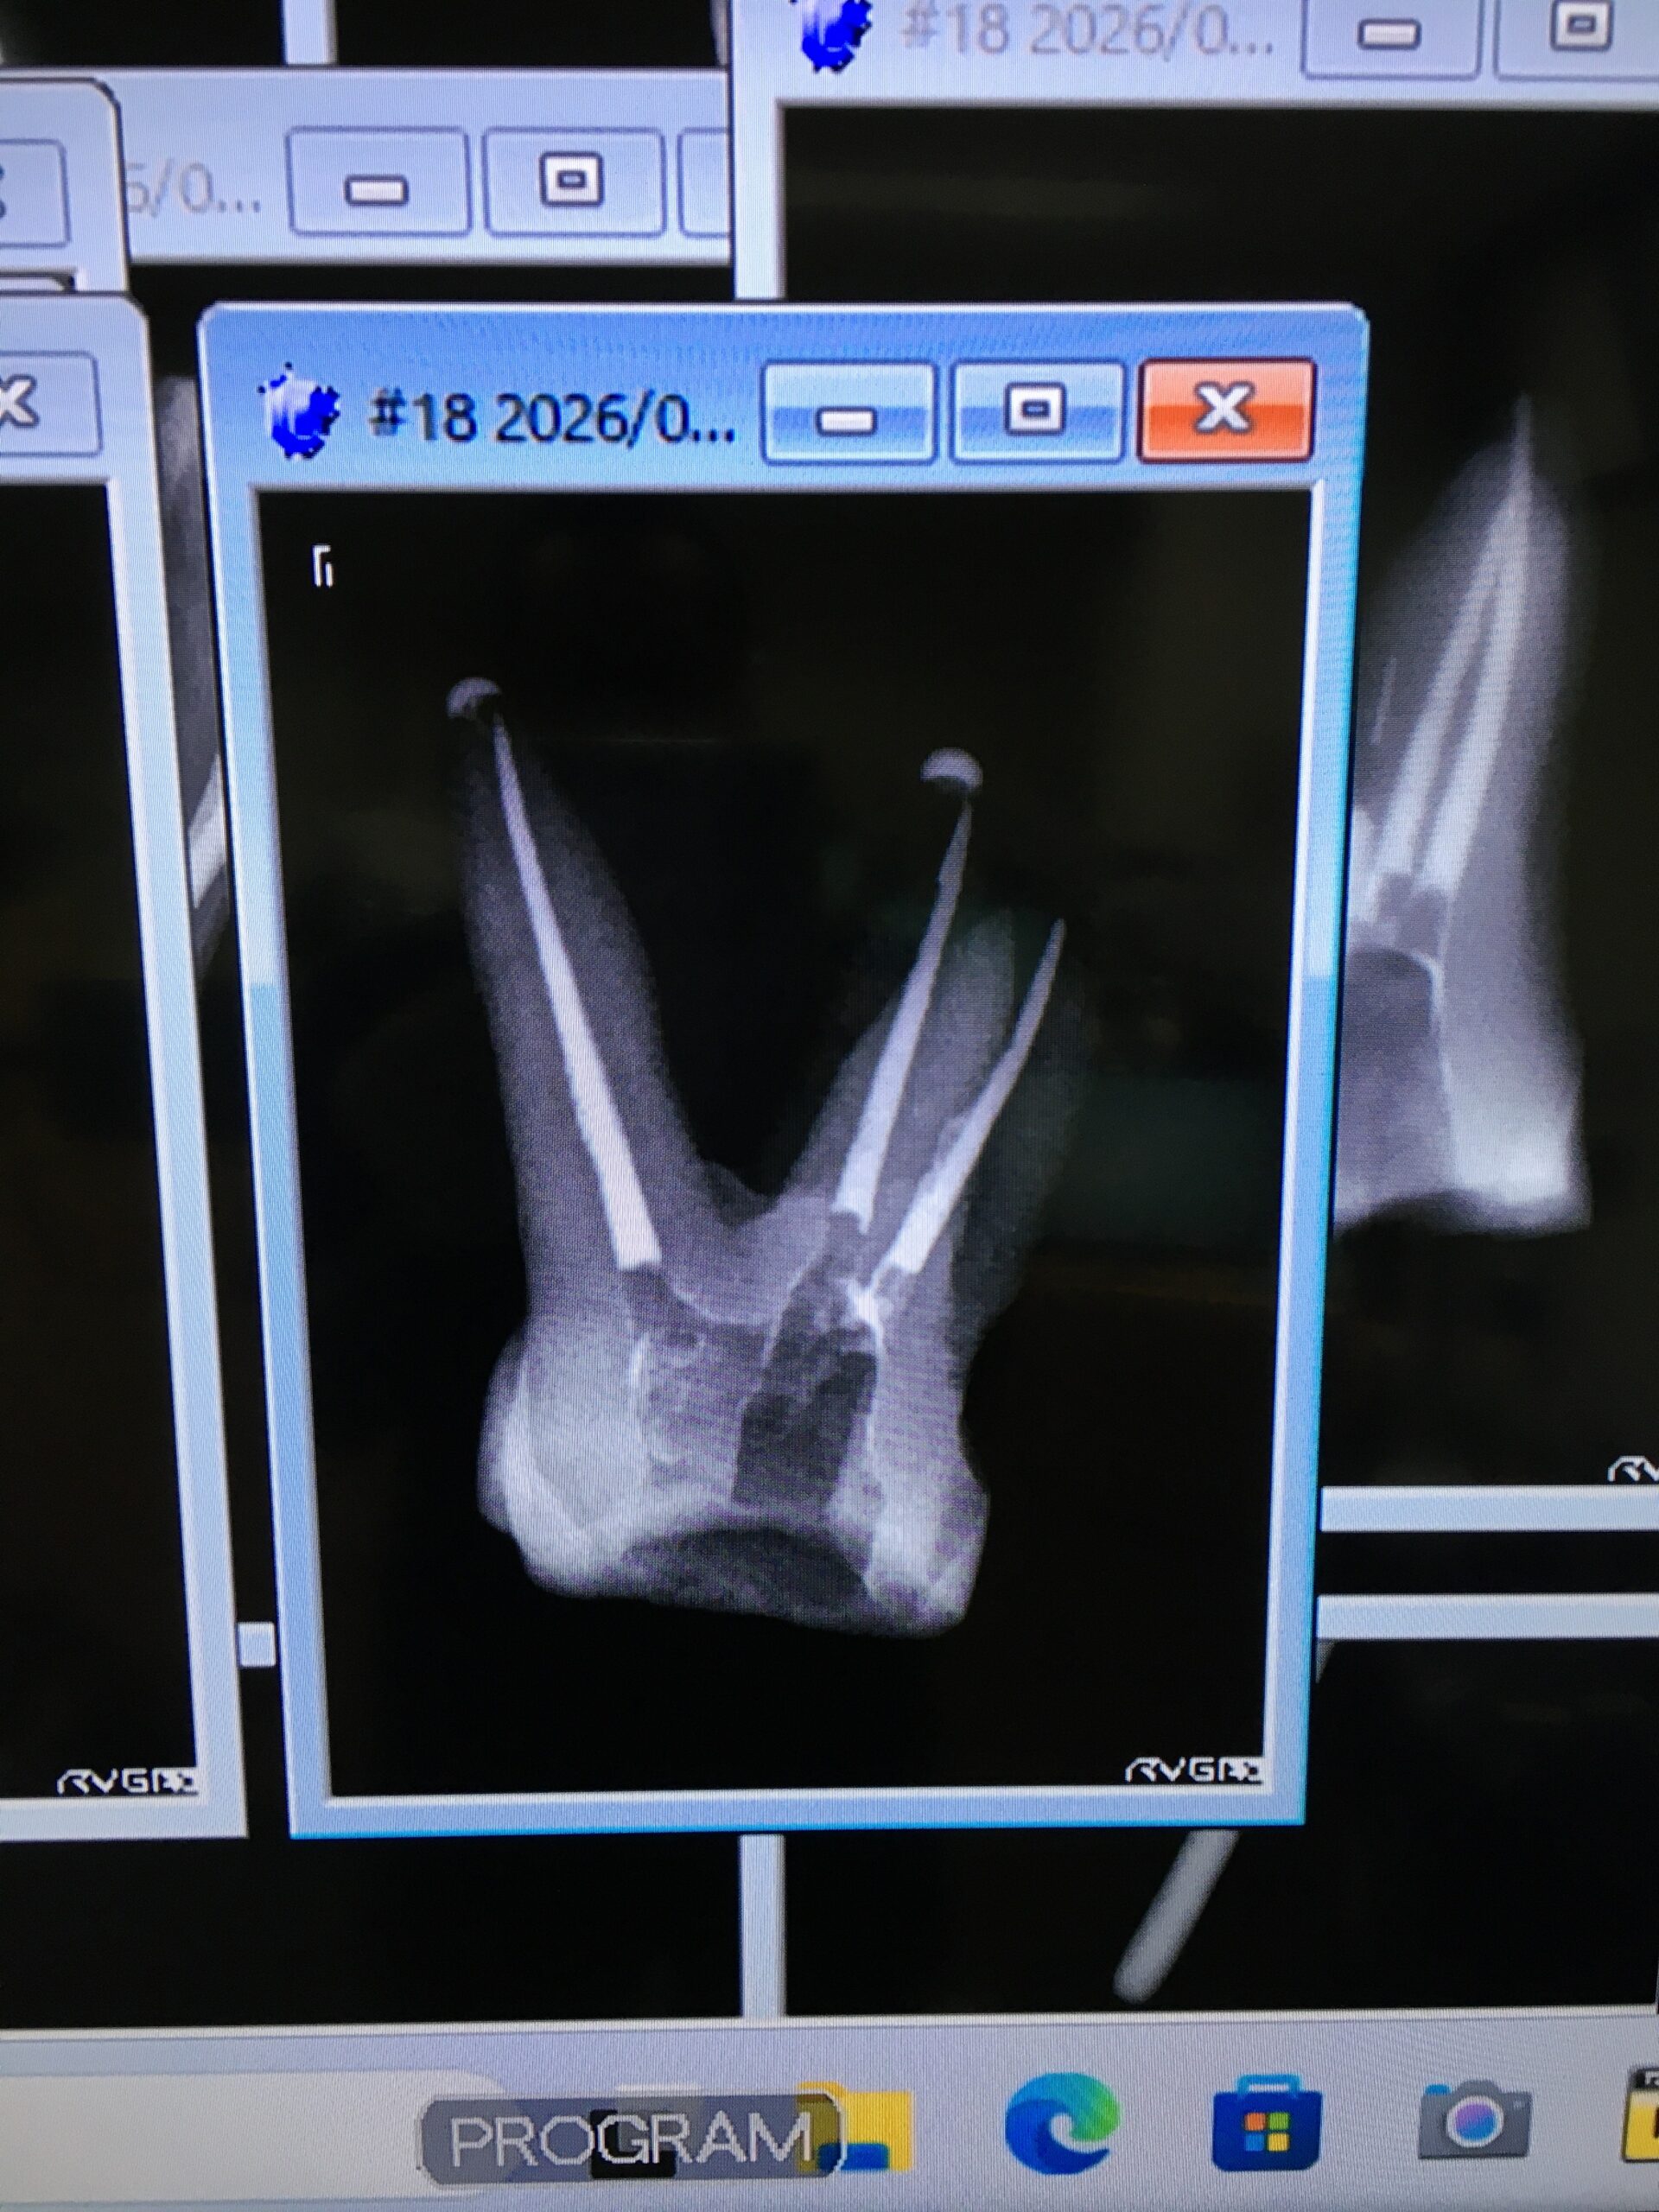

さてテストですが、ある程度の制限時間内に上下大臼歯1本ずつを根管充填まで行い、写真やレントゲン写真を見て、松浦先生を始め、受講生から評価して頂くといったものです。

折角の機会なので、上顎はMB根が途中から3方向に分かれている難しい歯を選択しました。結果はMB根の3方向へ分岐しているそれぞれの根管にシーラーが流れてくれるかと思いましたが、形成した主根管のみ根管充填がなされ、分岐した根管にはシーラーさえも流れ込んでくれませんでした。分岐した根管へ流れ込むこともあれば、流れ込まないこともある。この違いはなんだろう??

松浦先生にもみていただきましたが「これはしょうがない。臨床であれば、経過観察し、病変ができるようであれば歯根端切除へ移行する」と評価頂きました。

私なりの分析としては、主根管の形成時のデブリが分岐している根管に詰まったのではないか、ということです。

もちろん、洗浄は十分に行いながら根管形成していますが、分岐した方向にはPatencyできないので詰まるのでしょう。

分岐した方向へシーラーが流れる場合は、運良く分岐の方へデブリが詰まらなかった、根管充填時に分岐の方向へマスターポイント挿入時に圧力が適度にかかった、などの好条件が重なったものではなかろうか。